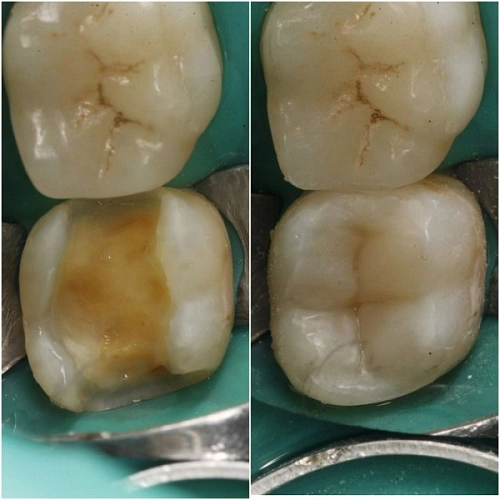

Под старой негерметичной пломбой оказалась глубокая кариозная полость.

Проведено лечение глубокой кариозной полости с реставрацией жевательной поверхности зуба.

При восстановлении таких глубоких полостей важно воссоздать анатомию зуба в соответствии со всем её изначальным микро и макро рельефом. При этом, очень важно правильно ввести вконтакт каждый бугор зуба.